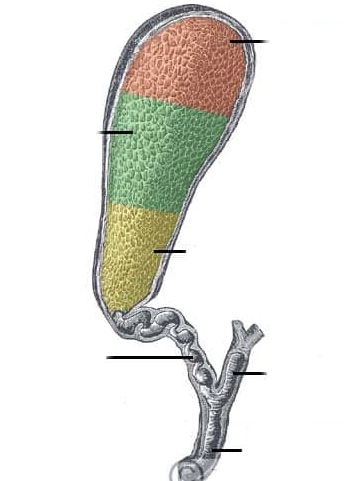

Fundus of gallbladder

orange highlight

Body of gallbladder

green highlight

Neck of gallbladder

yellow highlight

Cystic duct

pink highlight

Left hepatic ducts

Right hepatic ducts

Common hepatic duct

Common bile duct

Duodenal papilla within duodenum